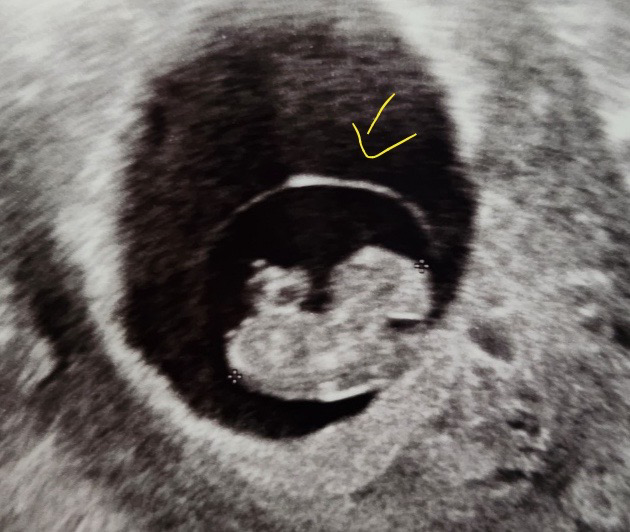

태아 초음파 상에서 보이는 이 얇은 테두리는 뭔가요?

사진 상으로 보이는 이 얇은 테두리가 뭔지 궁금합니다. 시험관 아기일 경우 글루일수도 있나요? 아니면 태반일까요? 아니면 양막인가요?

사진에 화살표하신 얇은 테두리

태아를 둘러싸는 막을 말씀하시는 것이죠? 양막입니다